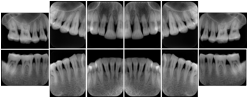

In most standard cases, images are oriented in structured layouts. These structured displays are useful to be shared between providers for reference purposes.

Table OO.1.1-1 shows structured display standard templates, where Viewset ID is based on the Japanese Society for Oral and Maxillofacial Radiology (JSOMR) classification provided by JIRA (Japan Medical Imaging and Radiological Systems Industries Association, www.jira-net.or.jp). Expected or typical teeth to be imaged location, region and designation codes are based on ISO 3950-2010, Dentistry - Designation system for teeth and areas of the oral cavity. For all the hanging protocols listed in OO.1.1-1, the value to use for Hanging Protocol Creator (0072,0008) is "JSOMR" and the value to use for Hanging Protocol Name (0072,0002) does not include "JSOMR" (e.g., "DL-S001A", not "JSOMR DL-S001A").

Table OO.1.1-1. Hanging Protocol Names for Dental Image Layout based on JSOMR classification